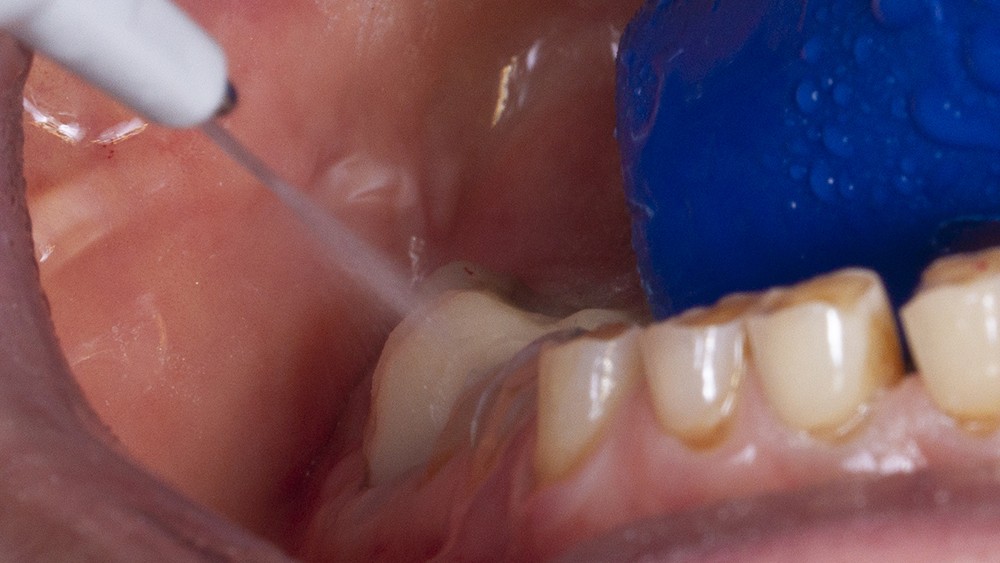

Enfin, la situation clinique peut imposer la dépose de restaurations prothétiques anciennes ; la reprise de traitements endodontiques ou encore la dépose de reconstitutions corono-radiculaires. Les résines chargées sont alors utilisées avec un scellement temporaire pour permettre la dépose régulière de celles-ci. Afin de faciliter la réalisation de ces éléments provisoires indépendants du reste du mock-up, un aménagement des espaces inter-dentaires jouxtant les restaurations sur le wax-up est recommandé. Cela est réalisé grâce à des outils permettant de marquer les embrasures occlusales et vestibulaires/linguales (ContactEZ, PRED) (fig. 4). Ces restaurations provisoires sont réalisées en tout premier lieu l ; e reste du mock-up est collé dans un deuxième temps. Ainsi, elles se révèlent être une référence supplémentaire pour le bon positionnement de la clé en silicone.